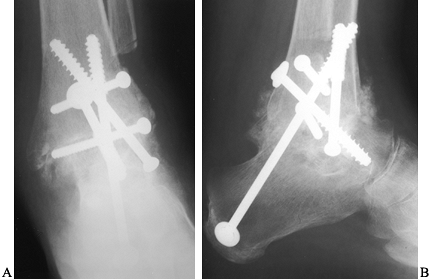

fusion is rarely indicated in rheumatoid arthritis. When significant

degeneration has occurred, surgical intervention may be necessary (Fig. 117.21). Whereas long-term evaluation of total ankle arthroplasty has revealed suboptimal results (47,69,88,99), newer uncemented components have yielded encouraging results (Fig. 117.22) (3,48).

![]() |

Figure 117.22. Rheumatoid arthritis of the ankle. A: AP radiograph. B: Lateral radiograph. C: Postoperative lateral radiograph after total ankle arthroplasty. D: Lateral radiograph.

|